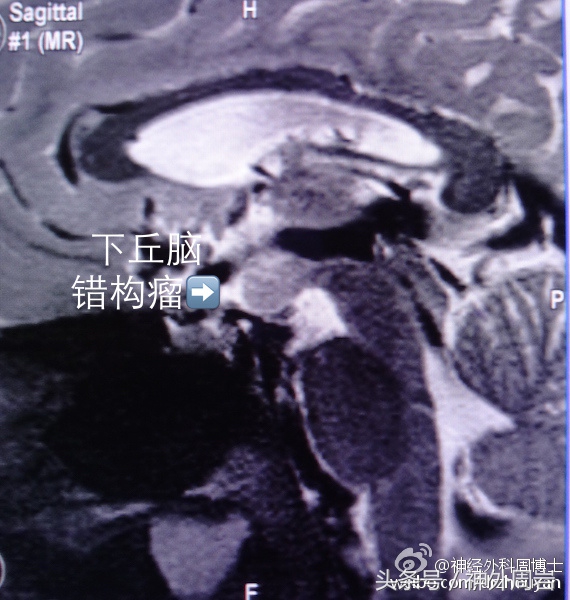

主要发生在5岁以下,除了发笑以外,无情绪变化和意识障碍,几乎不伴有其他癫痫症状,多有下丘脑错构瘤,如进一步压迫下丘脑,患者还可出现性早熟症状。

这类患者对药物治疗反应不好,预后差,早期手术切断错构瘤与周围组织的病理联系可减少或终止发作。